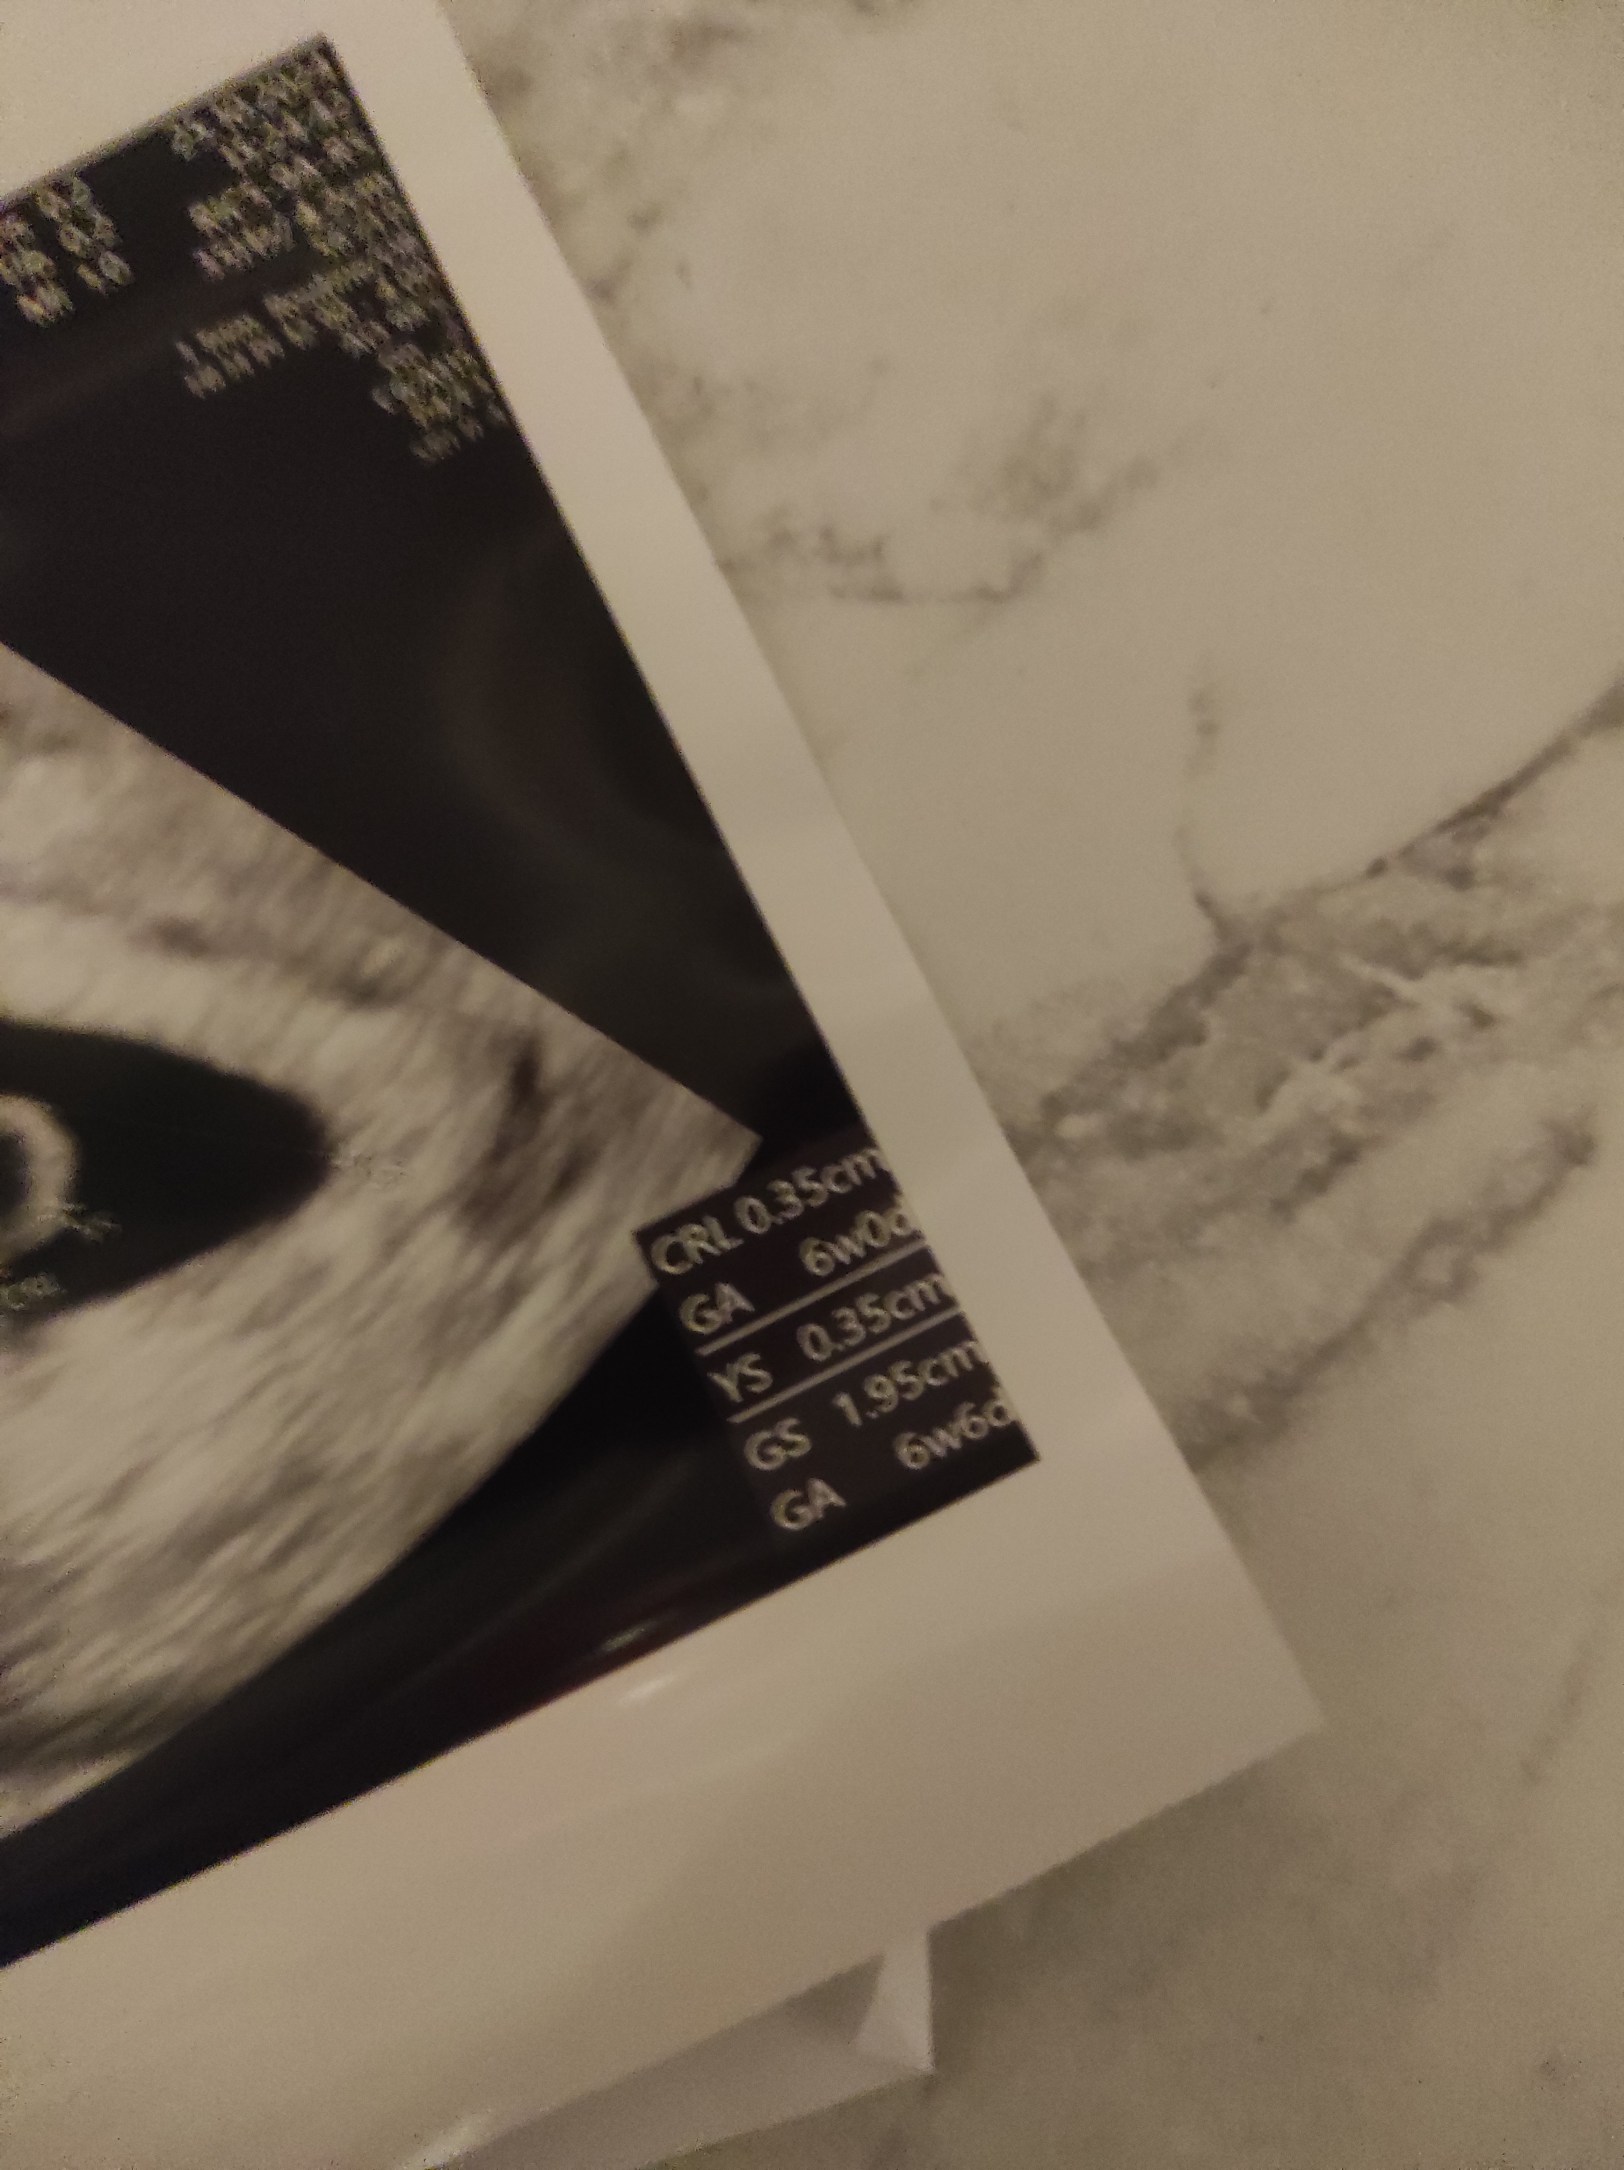

Ten niżej to raczej z daty OM, a ten 6+0 to po zmierzeniu zarodka. Nie mówił Ci nic, że ciąża tydzień młodsza?Kto mi podpowie, bo ja byłam tak zakręcona na wizycie, że połowy nie zarejestrowałam co do mnie mówił lekarz.Który wynik w tygodniach jest prawidłowy, bo są dwa na zdjęciu USG 6w0d i niżej 6w6d.Zobacz załącznik 1669186

Mówił, że nie 8 tydzień a 7 tydzień , a byłam na wizycie jak było 7+4. Dlatego już sama nie wiem.Ten niżej to raczej z daty OM, a ten 6+0 to po zmierzeniu zarodka. Nie mówił Ci nic, że ciąża tydzień młodsza?

No to bym się skłaniała do wartości 6+6 jednakMówił, że nie 8 tydzień a 7 tydzień , a byłam na wizycie jak było 7+4. Dlatego już sama nie wiem.![]()

CRL - długość odpowiada 6+0 a pęcherzyk ciążowy 6w6. Pewnie termin będzie wyznaczony na prenatalnych. ;-)Kto mi podpowie, bo ja byłam tak zakręcona na wizycie, że połowy nie zarejestrowałam co do mnie mówił lekarz.Który wynik w tygodniach jest prawidłowy, bo są dwa na zdjęciu USG 6w0d i niżej 6w6d.Zobacz załącznik 1669186